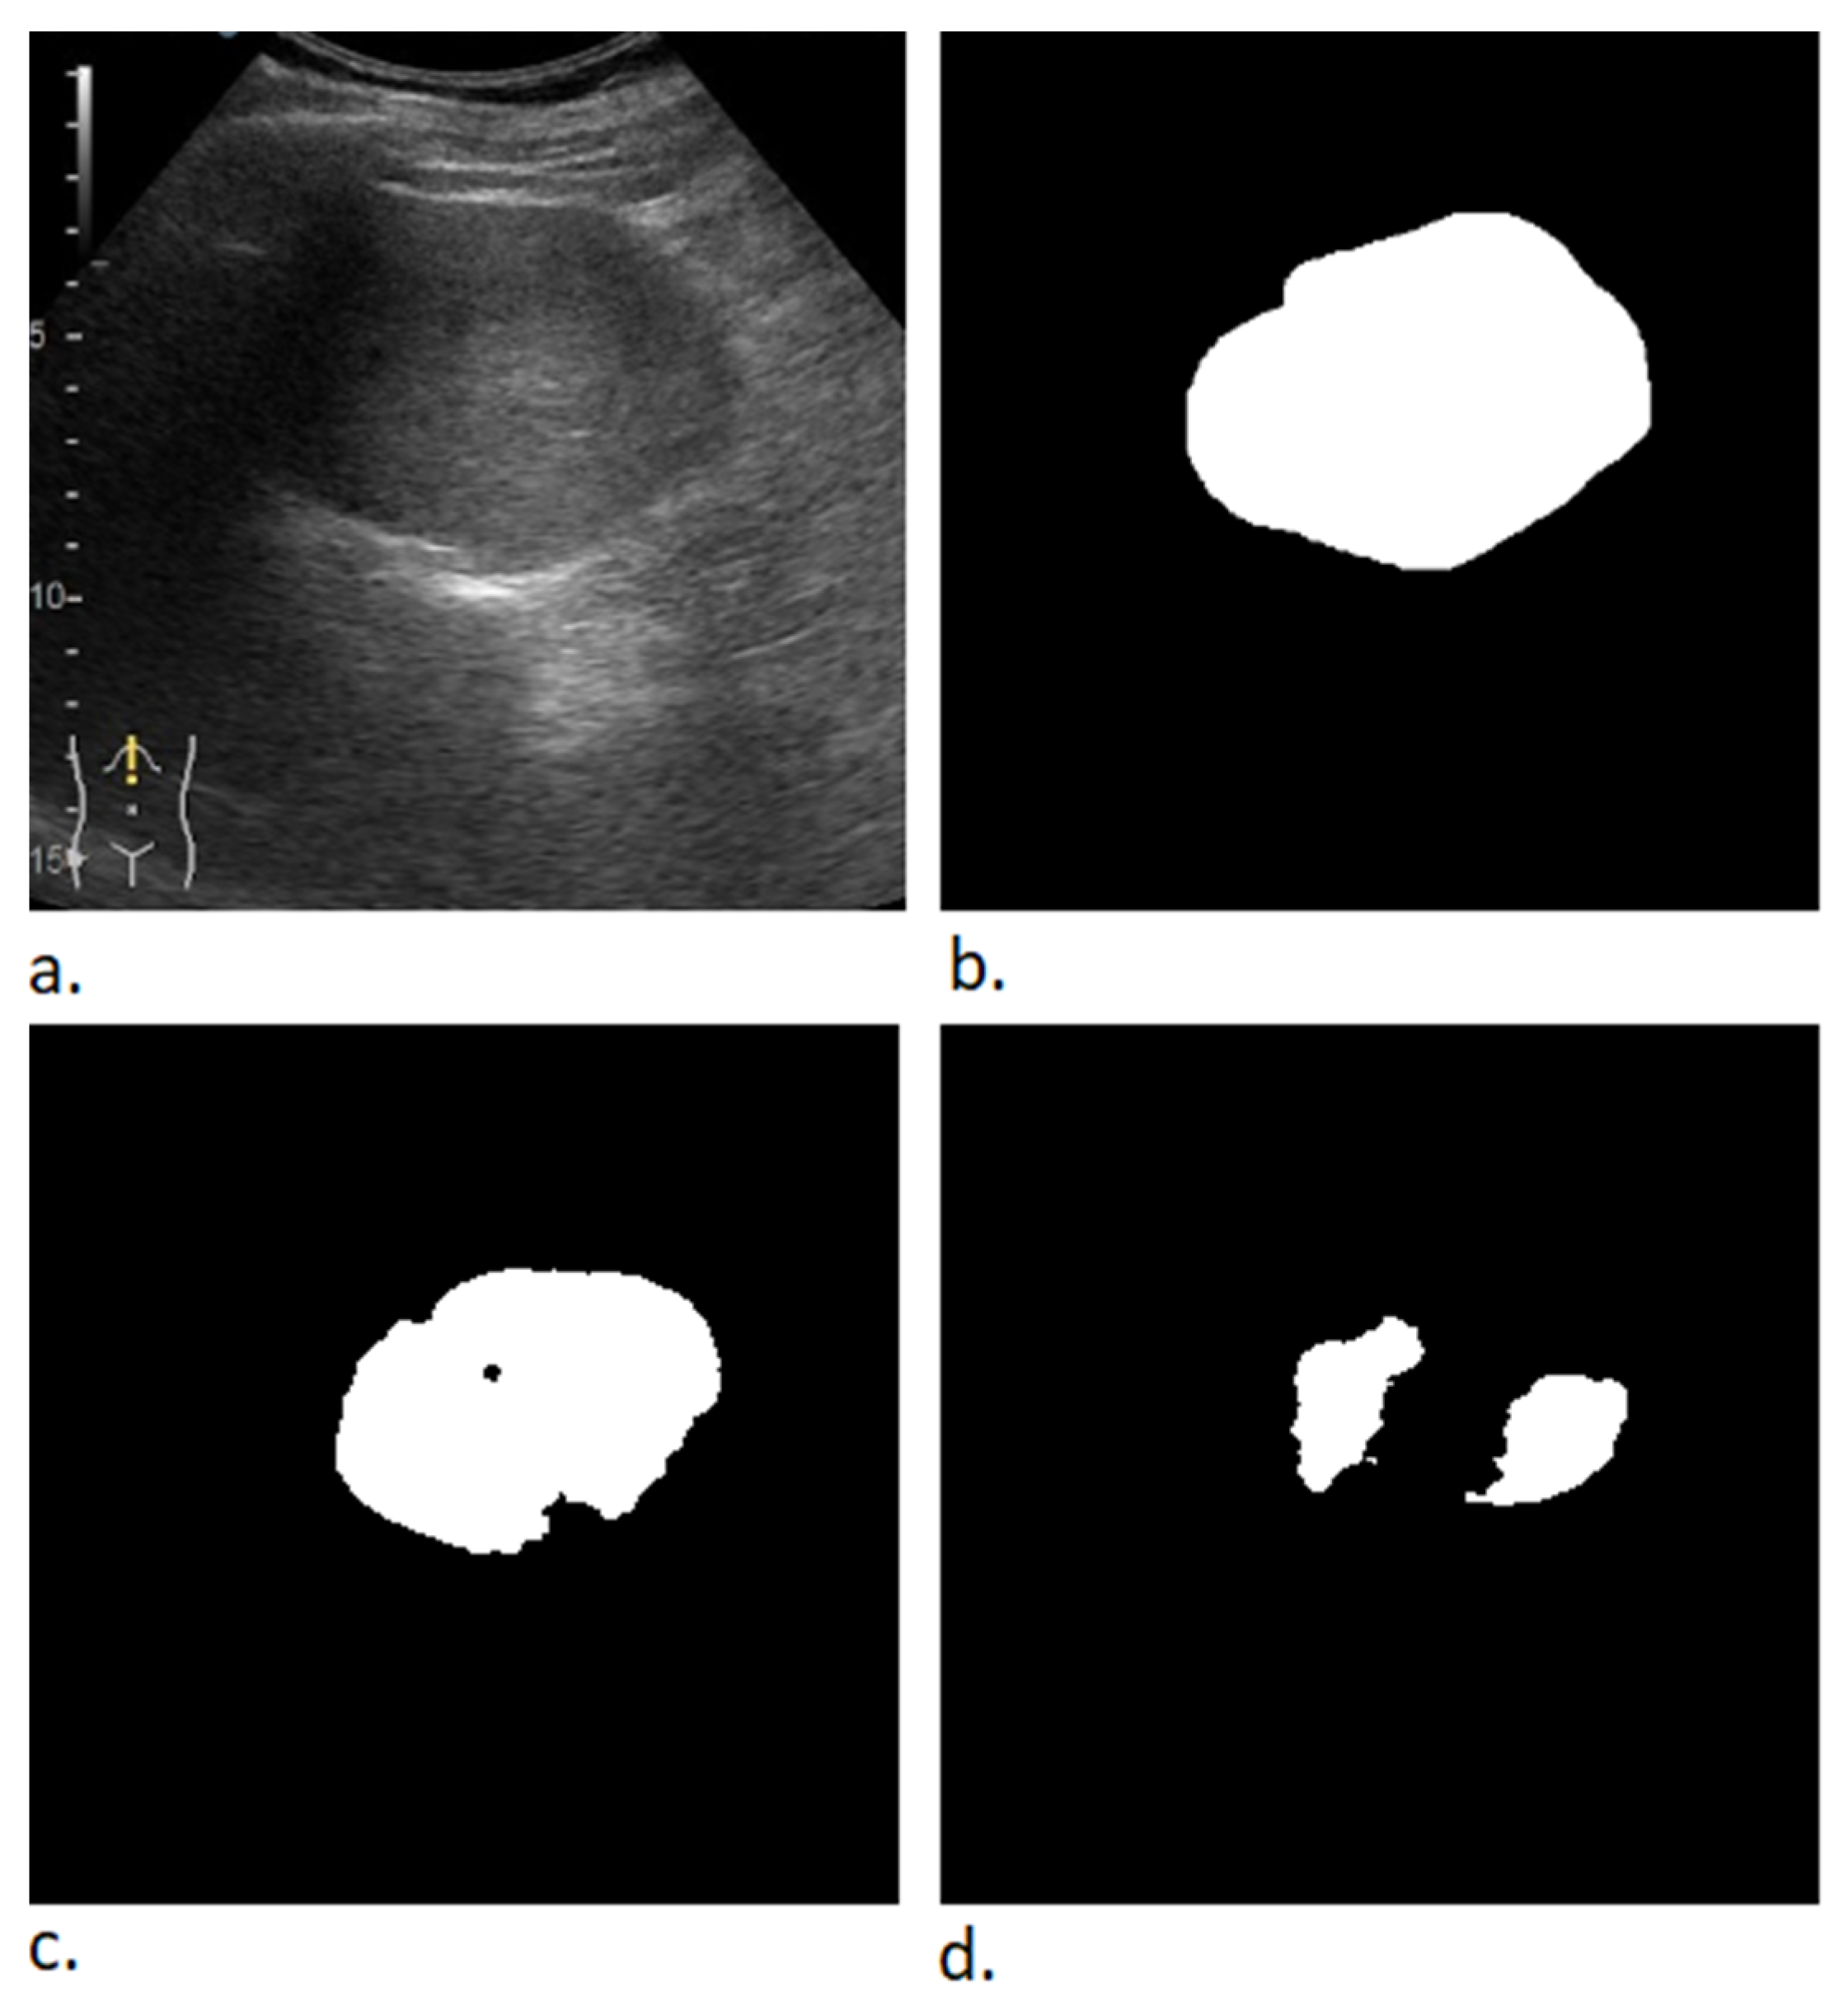

2.2. Data Preprocessing

| Algorithm 2. Mask creation (binary image) | |

| current_image ← obtain current image while current_image is not null do: mask ← new Image(current_image.width, current_image.height, values = 0) for each object in annotation_list do: roi ← object.getROI() roi.fill(values = 1) mask ← mask bitwise and roi mask_filename ← string concatenation (current_image.name, “-mask”) save image to disk (mask, mask_filename) | |